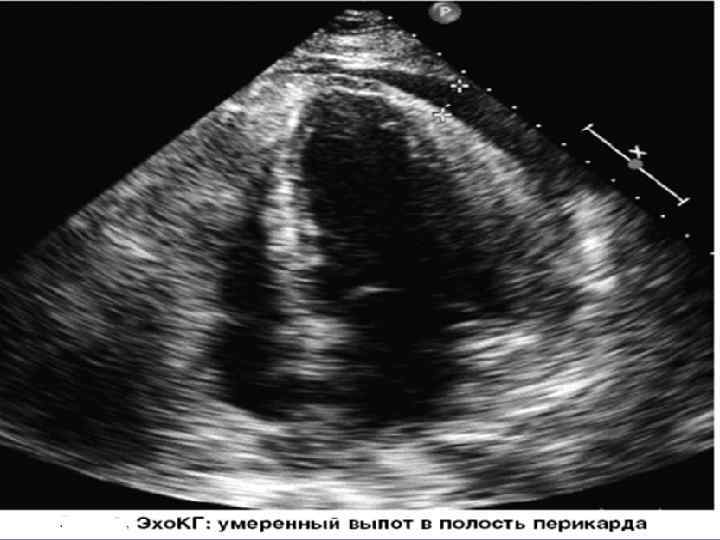

ЭХОКГ • Увеличение количества жидкости в перикарде • Расслоение листков перикарда от 3 мм до 2 -3 см • Яркое свечение листков перикарда • Утолщение листков перикарда • Появление диастолической дисфункции миокарда • Втяжение стенки правого желудочка при тампонаде сердца

ЭХОКС • Выпот в полости перикарда может располагаться циркулярно вокруг сердца или инкапсулированно перед отдельными полостями сердца. • При отсутствии спаек и свободном движении жидкости в полости перикарда сепарация листков максимальна позади левого желудочка и у верхушки сердца, постепенно уменьшается и исчезает на уровне основания сердца. • При выпоте отмечается повышенная экскурсия задней стенки ЛЖ, а у части больных гиперкинезия передней стенки правого желудочка и межжелудочковой перегородки.

• Основное диагностическое значение имеет диастолическое расхождение листков перикарда, которое может быть выявлено при количестве выпота, превышающем 15– 35 мл. Градации выраженности выпота: • 1) малый (расхождение листков перикарда <10 мм); • 2) умеренный (≥ 10 мм кзади); • 3) большой (≥ 20 мм); • 4) очень большой (≥ 20 мм плюс симптомы сдавления сердца) - тампонада

ЭХОКС Полуколичественная оценка объема перикардиального выпота: • циркулярное эхонегативное пространство (сумма величин сепарации листков перикарда по передней и по задней поверхности сердца в конце диастолы) - • менее 5 мм — незначительное количество жидкости (менее 50 мл); • 5– 10 мм — небольшое количество (50– 100 мл); • 10– 20 мм — умеренное количество (100– 300 мл); • более 20 мм — значительное количество (более 300 мл).

ЭХОКС • При наличии небольшого выпота в перикарде обнаруживается относительно свободное от эхо-сигнала пространство между задней частью перикарда и задней частью эпикарда левого желудочка. • При большем объеме выпота это пространство располагается между передней частью перикарда правого желудочка и париетальной частью перикарда непосредственно под передней грудной стенкой.